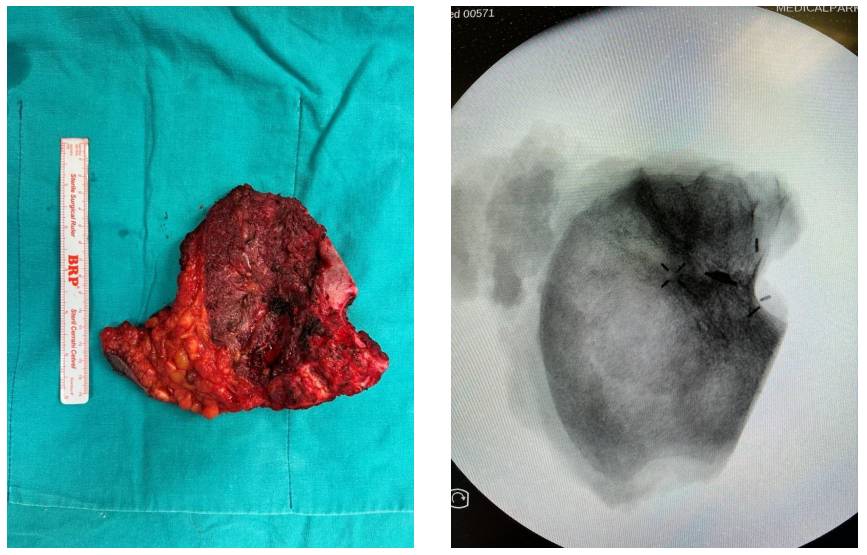

Ameliyat Esnası: Rezeksiyon dokusunun klinik ve skopi görüntüsü